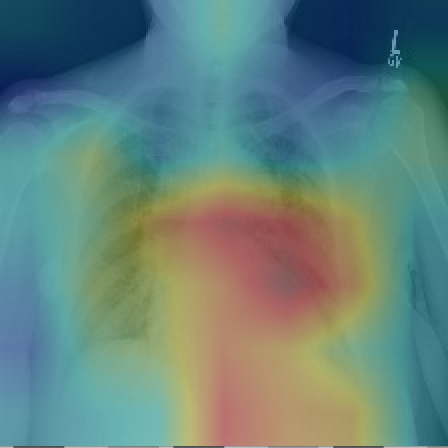

与此同时,为了解网络预测准确程度,网络还使用类激活映射(CAM)生成热图,以便可视化图像中与疾病最相关的区域[14]。为了生成CAM,将图像送到完全训练的网络中,并提取出最后一层卷积层输出的特征图。假设是第k个特征映射,并且令是第k次特征映射导致疾病c在最终分类层中的权重。模型通过使用相关权重对特征映射进行加权求和得到一个最明显的特征热图,用于将图像分类为疾病c。虽然模型网络最终能得到病理的热图,热值较高的区域即为可能发生疾病的区域,但并没有给出切割区域的准确结果,无法与原始切割效果做对比评判性能。

基于该模型的思想,单独的DenseNet网络能够得到较好的分类效果,并可以通过CAM技术画出网络学习到的热图来对病理区域进行分析。利用与DenseNet具有相似性质不仅模型深,同时复杂度也较低的ResNet网络也会得到类似的结果,其相关模型介绍见下一节。